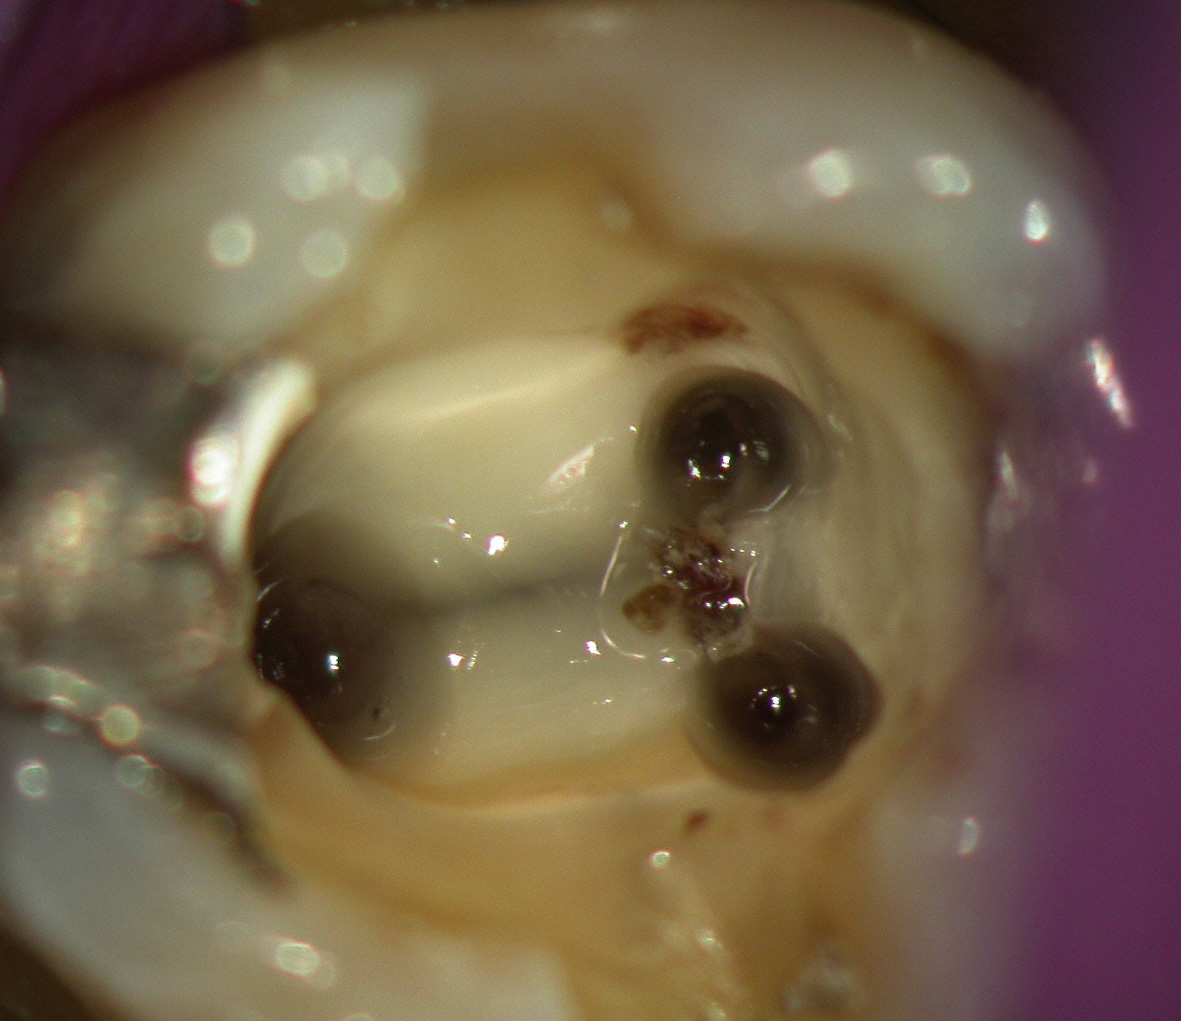

Unter örtlicher Betäubung ist die Behandlung in der Regel schmerzfrei. Nach Entfernung der Karies und der Schaffung eines Zugangs zur Pulpenhöhle werden die Kanaleingänge dargestellt und die Länge jedes einzelnen Kanals wird möglichstexakt unter Anwendung von Röntgen ausgemessen. Abhängig vom zu behandelnden Zahn kann die Anzahl der Kanäle stark variieren. So haben Frontzähne bspw. nur einen Kanal, während Seitenzähne im Oberkiefer (Molaren) meist 3 Kanäle besitzen.

Da die Kanaleingänge oft sehr eng sind, werden häufig stark vergrößernde Lupenbrillen verwendet.